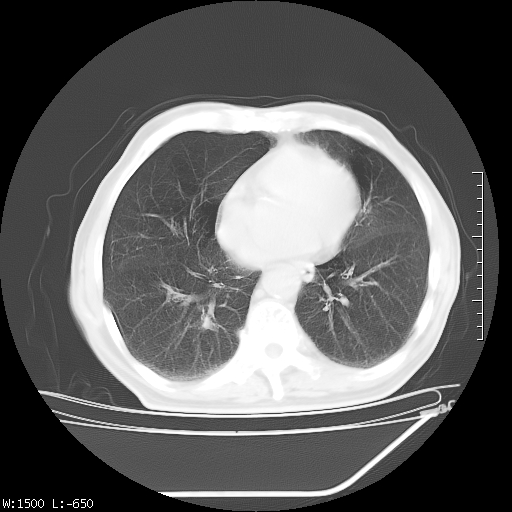

标题: CT23994:男、72、咳嗽、气短两月余,近来消瘦。 [打印本页]

标题: CT23994:男、72、咳嗽、气短两月余,近来消瘦。

右上肺实变,与胸膜关系密切,右肺容积缩小,隆突下淋巴结增大,考虑1 肺结核 2 肺癌

右上肺大片状密度增高影,与胸膜关系密切,内见低密度透亮影,胸膜下可见三角形不张影,左下肺沿支气管走形结节影,纵膈内淋巴结显示。考虑结核并疤痕性不张可能性大,建议穿刺活检,排除肺泡癌。